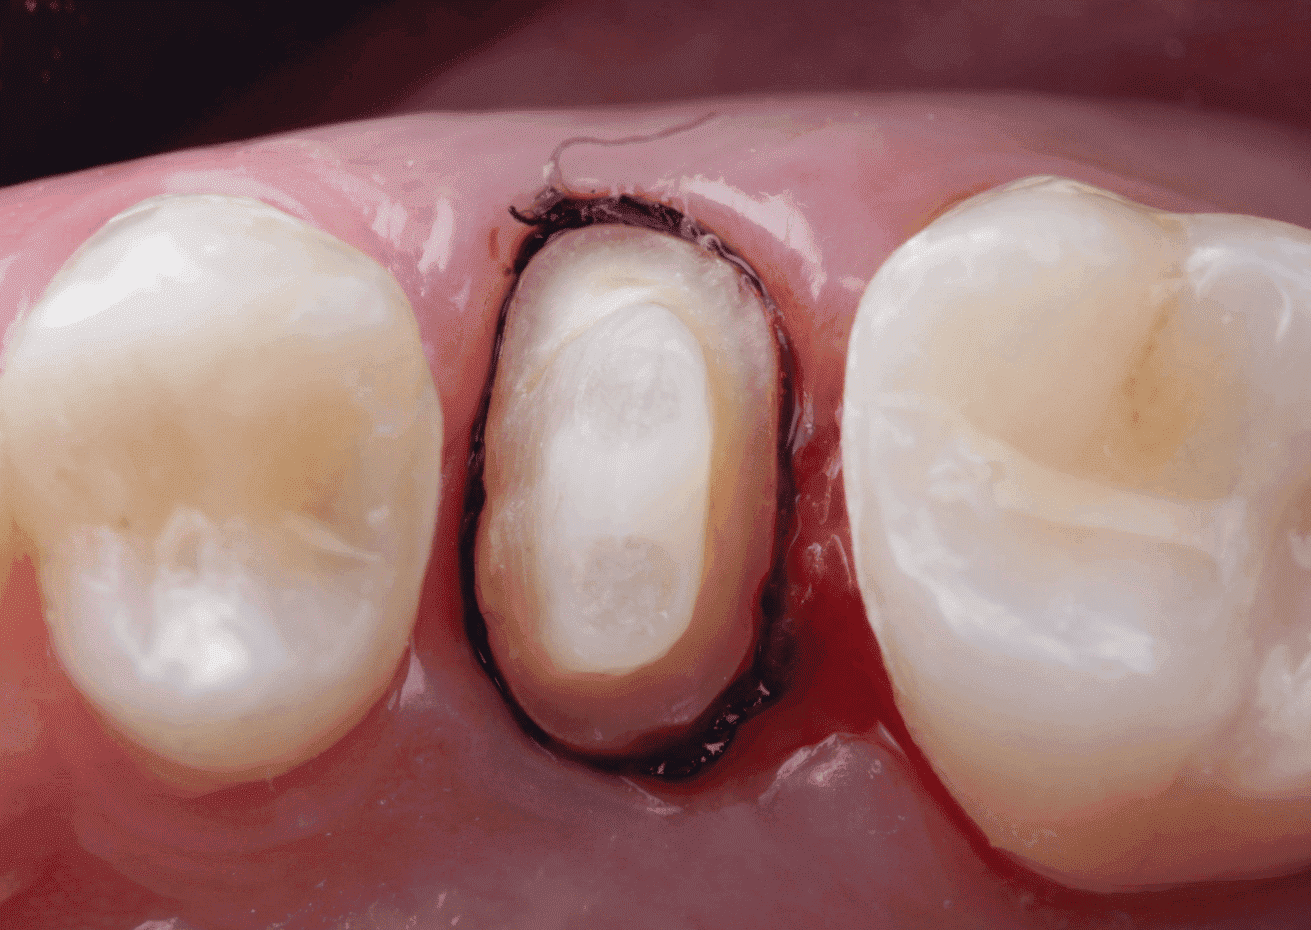

No planejamento reabilitador, foi reabilitado com dois pinos Whitepost SYSTEM cimentados com a combinação de sistema adesivo Ambar Universal APS e cimento resinoso dual Allcem CORE, que também foi utilizado para construção do núcleo de preenchimento.